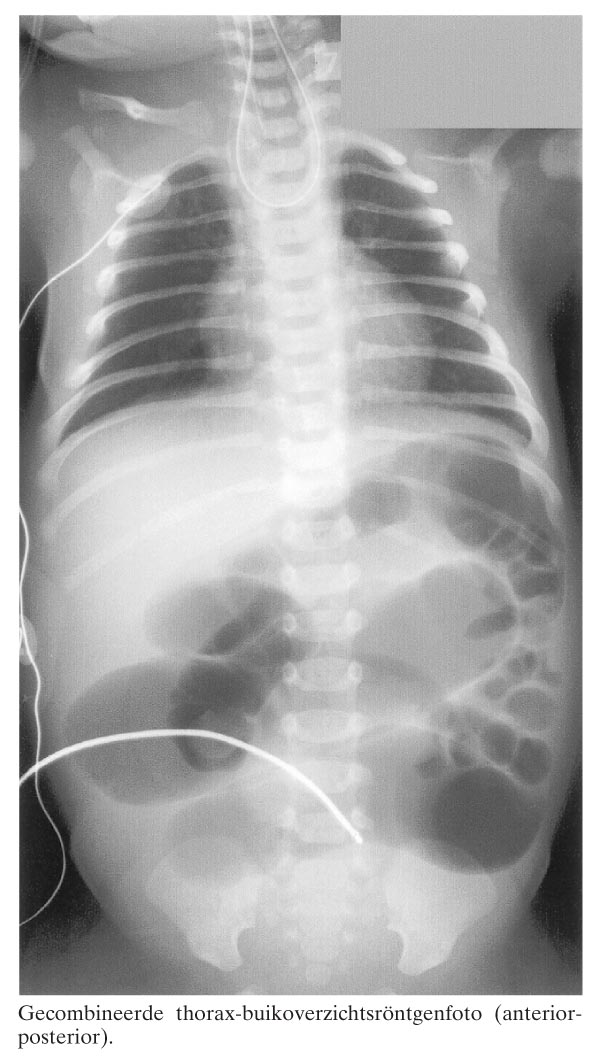

Een aterm geboren mannelijke neonatus werd postnataal naar ons ziekenhuis overgeplaatst in verband met ‘bellenblazen’ en omdat het opvoeren van een maagsonde bij hem niet mogelijk was. Bij lichamelijk onderzoek viel op dat het kind uiterlijke kenmerken had van het syndroom van Down. Omdat een oesofagusatresie werd vermoed, werd een gecombineerde thorax-buikoverzichtsröntgenfoto gemaakt (figuur). Hierop was te zien dat de maagsonde opkrulde in de oesofagus en dat er lucht was in de darmen, hetgeen de diagnose ‘oesofagusatresie met distale tracheo-oesofageale verbinding’ bevestigde. Opvallend was dat er 11 paar ribben waren. Dit versterkte in röntgenologisch opzicht het klinische…